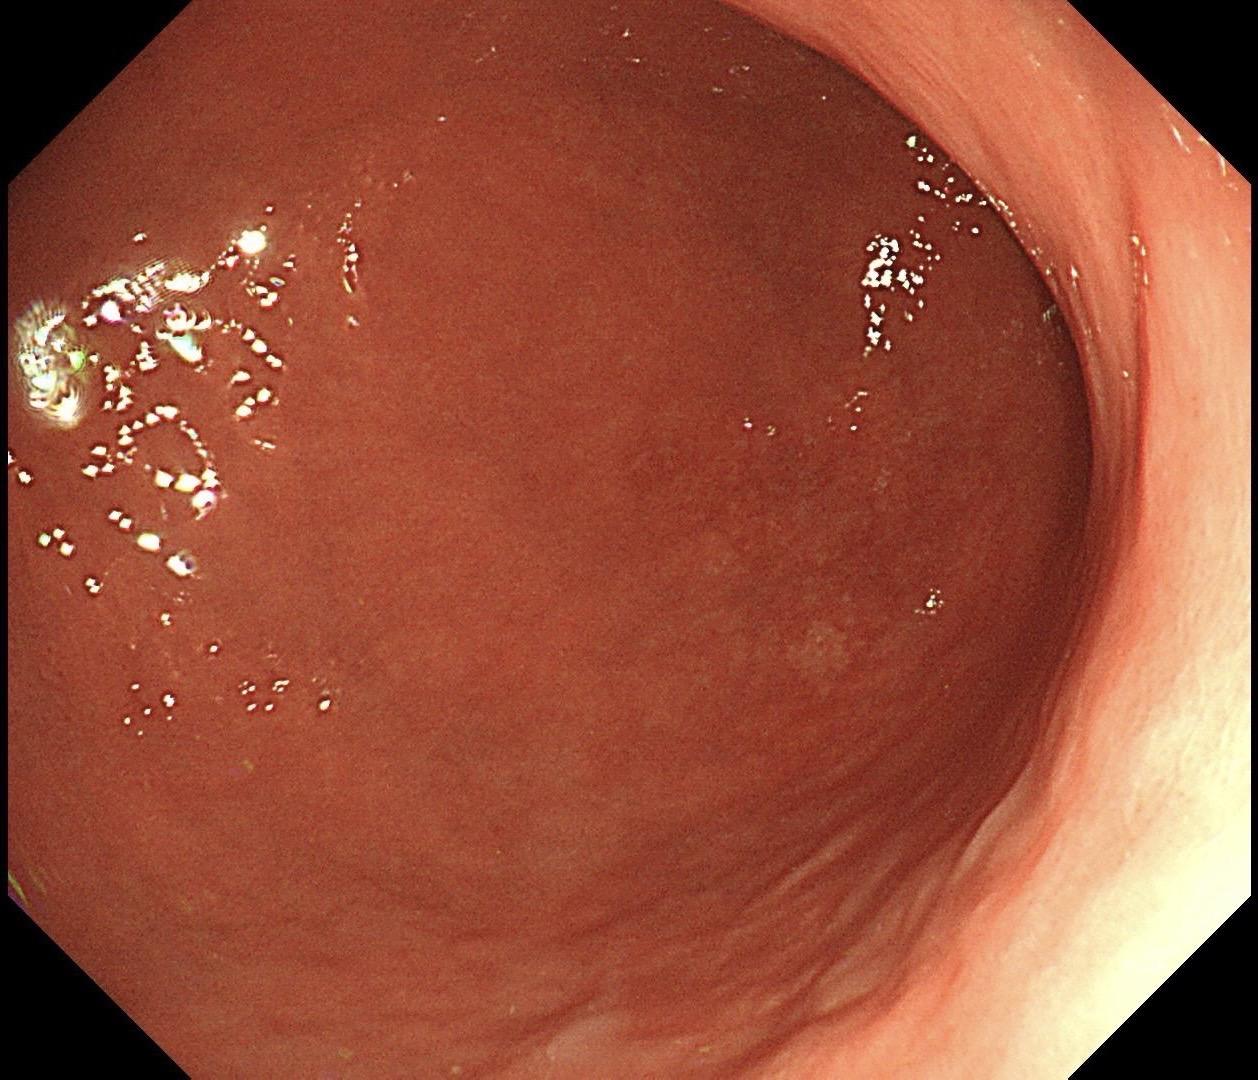

男,40岁,胃双发褪色调病变。慢性胃炎复查,3年前胃镜未见异常,Hp阳性背景,萎缩不明显,胃体下部大弯见一褪色调病变,浅凹陷,5mm左右,换用放大内镜观察,表面结构缺失,血管异型明显,未分化可能性大……胃窦后壁见一白斑,无高度差,NBI浅茶色,放大草草看了下,似有边界,IP增宽,活检待病理……小哥哥胖得几乎没脖子,腹式呼吸太明显~😖